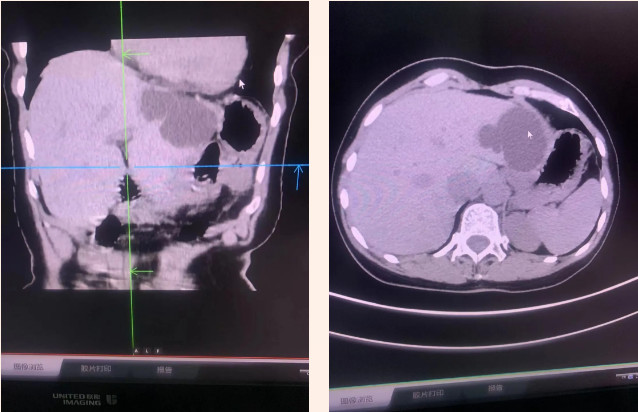

据了解,术前外科医生对患者CT三维重建的影像进行了认真研究,发现病灶囊壁向上以达隔顶,向外与胃窦部紧邻,而且已达肝左叶包膜下,壁薄如纸,随时有破裂引发腹腔出血的可能,为考虑患者身体健康出发,决定由外科主任主刀,为患者手术切除肝囊肿,以解除患者病痛。